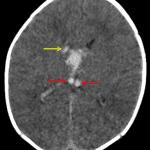

Age: 4 days (term)

Sex: Female

Indication: Seizure

Findings

- Abnormal hyperdensity in the internal cerebral veins, the vein of Galen, and likely in portions of the thalamostriate veins

- Adjacent acute hematoma in the third and lateral ventricles and at the right caudothalamic junction

- Bilateral cephalohematomas

Diagnosis

- Deep vein thrombosis with intraventricular and right caudothalamic region intraparenchymal hemorrhage

- Cephalohematomas

Abnormal hyperdensity in the internal cerebral veins, the vein of Galen, and likely in portions of the thalamostriate veins concerning for deep vein thrombosis. Resultant acute intraventricular hemorrhage in the third and lateral ventricles and intraparenchymal hemorrhage at the right caudothalamic junction. No midline shift, herniation, or hydrocephalus.

Bilateral cephalohematomas.